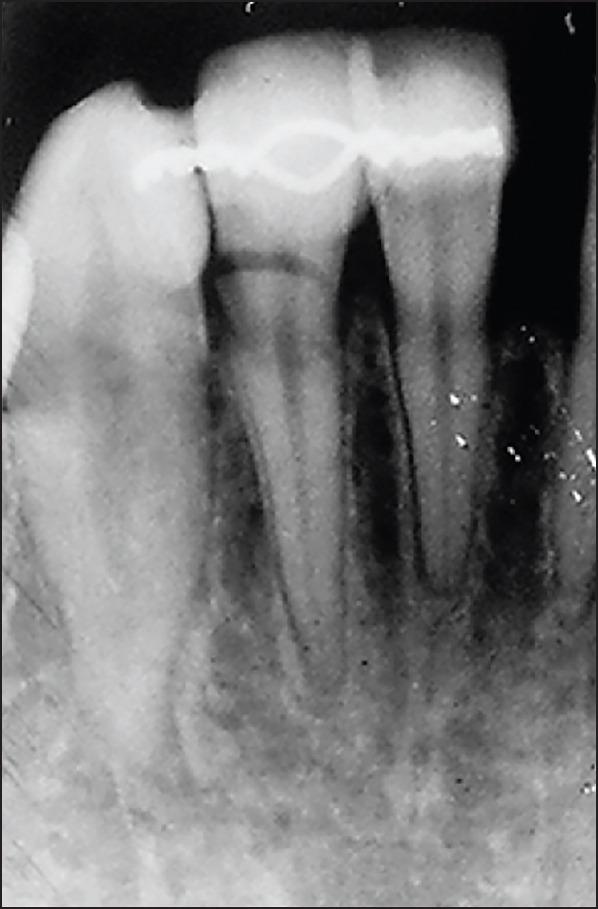

This case report describes the treatment of a double root fracture of a lateral mandibular incisor and its follow- up over 3.5 years. The reason for the consultation was a tooth mobility following a fall that had occurred 2 days earlier. A test of pulp vitality for tooth 42 was positive. Periodontal probing at the level of the gingival sulcus confirmed the intactness of the epithelial attachment. Retro-alveolar radiographic examination revealed a double root fracture of tooth 42. A semi-rigid extra-coronal splinting was performed and a light grinding of the incisal edge of tooth 42 was then carried out in light of the dislocation of the coronal fragment, and the occlusion was checked with a strip of articulating paper. The outcomes at 6 months revealed that pulp vitality was still preserved, consolidation of the apical fracture had occurred, and the coronal root fracture was starting to heal. The 1-year, 2-year and 3-year follow ups revealed preserved pulp vitality, an absence of a fracture line in apical images, and no root resorption. This case report provides evidence for the preservation of vitality in the setting of a double root fracture.

本病例报告描述了一例下颌侧切牙双根骨折的治疗及其3.5年的随访情况。会诊原因是2天前摔倒后牙齿松动。对42号牙的牙髓活力测试呈阳性。在龈沟水平进行牙周探诊证实上皮附着完整。牙槽后位X线检查显示42号牙双根骨折。进行了半刚性冠外夹板固定,然后根据冠部骨折块的移位情况对42号牙的切缘进行了轻度打磨,并用一条咬合纸检查了咬合情况。6个月时的结果显示牙髓活力仍然保留,根尖骨折已愈合,冠根骨折开始愈合。1年、2年和3年的随访显示牙髓活力保留,根尖影像中无骨折线,且无牙根吸收。本病例报告为双根骨折情况下保留牙髓活力提供了证据。